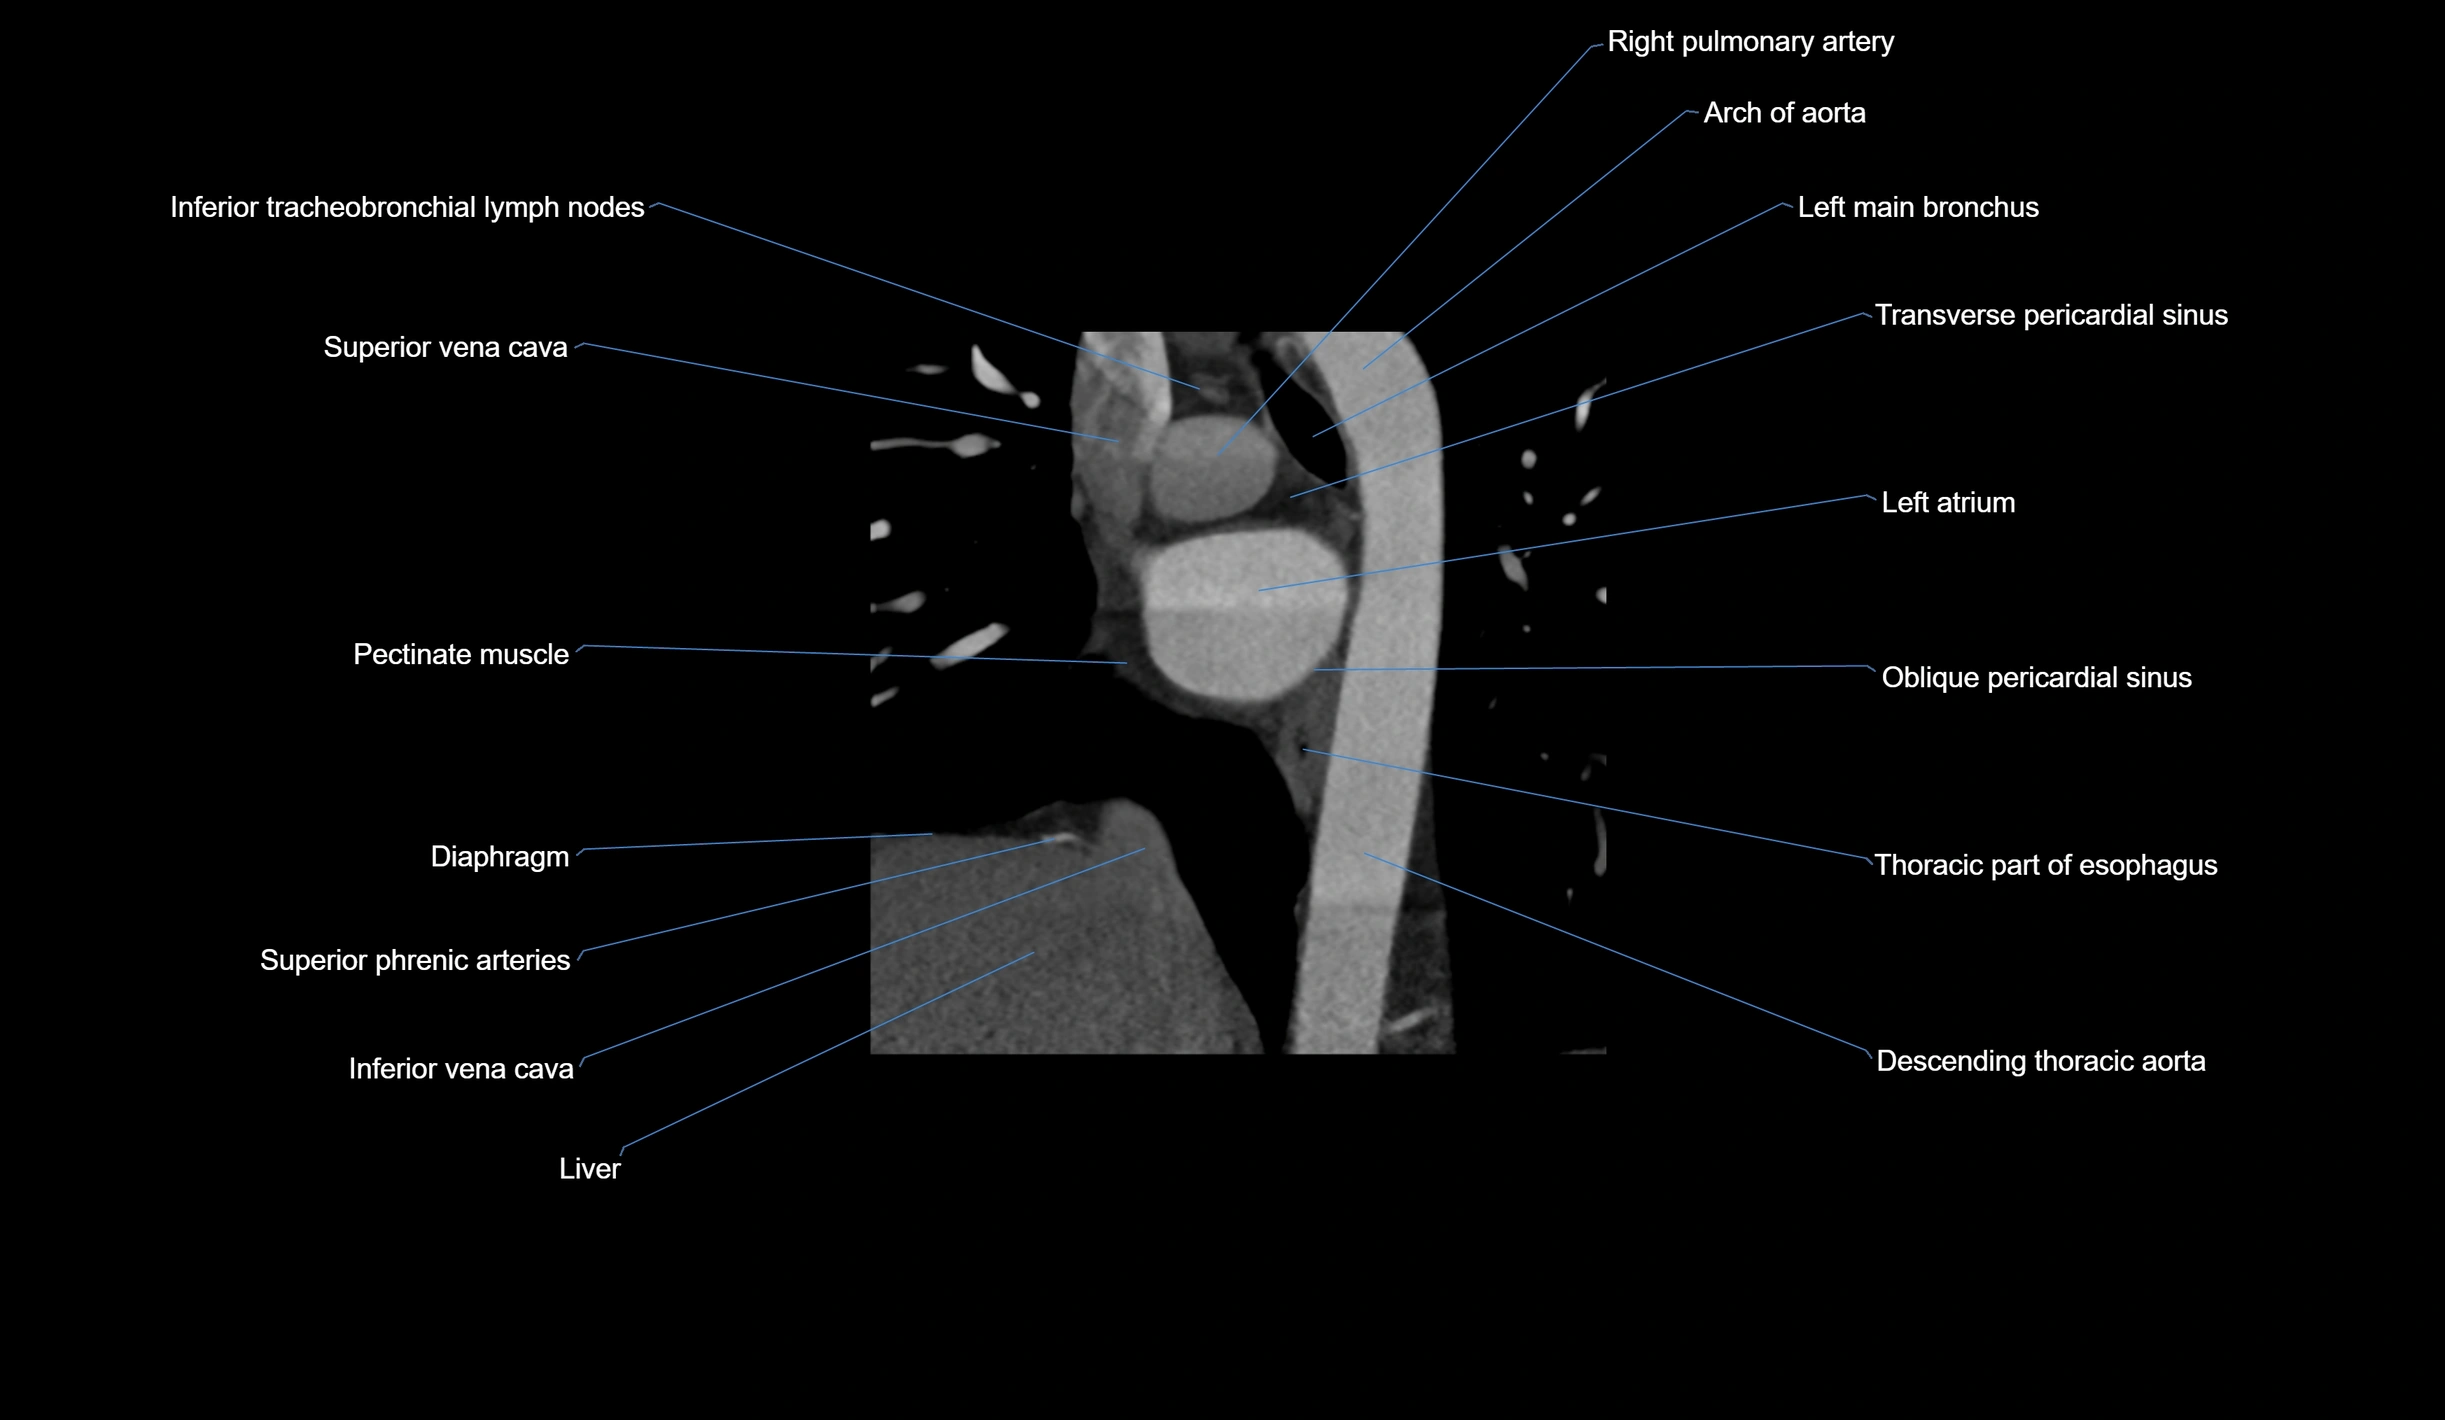

- Acute marginal artery (AM)

The acute marginal artery (AM) is one of the main branches of the right coronary artery (RCA). It typically arises from the mid to distal segment of the RCA and courses along the acute margin (right inferolateral border) of the right ventricle. The AM artery runs within the epicardial fat and supplies blood primarily to the right ventricular free wall.

The number and size of AM branches vary: most individuals have one dominant acute marginal artery, but some may have multiple smaller branches. The vessel is of high clinical importance in right ventricular infarction, since occlusion or disease of the RCA or AM branch can compromise right ventricular contractility and systemic venous return.

CT Coronary Angiography (CCTA):

-

Best non-invasive modality for acute marginal artery visualization

Shows origin, course along the acute margin, and right ventricular branches

Detects stenosis, occlusion, calcified and non-calcified plaques, aneurysm, or anomalous course

Multiplanar reformats and 3D reconstructions help in pre-PCI and surgical planning

Critical for assessing right ventricular infarction risk in RCA disease

CT images